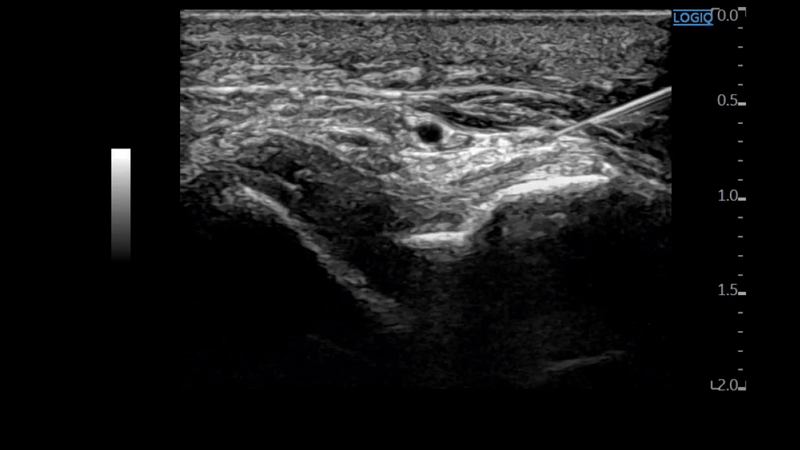

염증으로 들러붙은 유착 부위를

초음파로 보면서 시술하는 약침을

이라고 합니다.

구허혈에서 신경과 혈관을 찌르지 않게

안전한 경로로 을 시술합니다.

유착으로 들러붙은 인대를

으로 떼어냅니다.